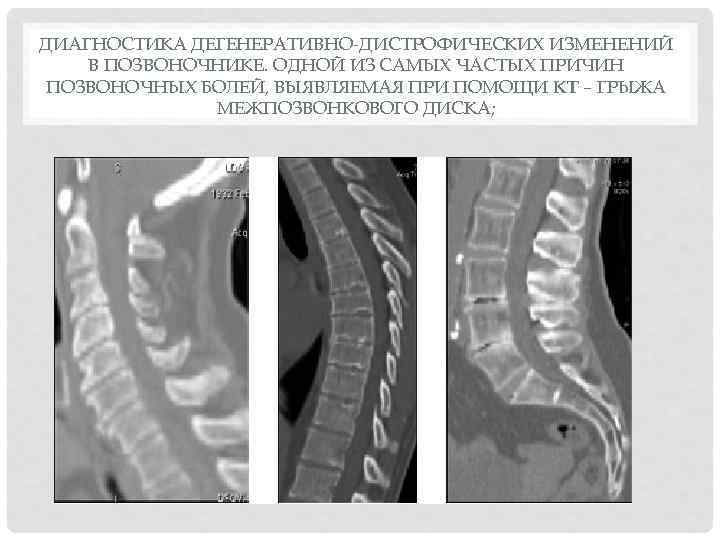

Мрт картина дегенеративно дистрофических изменений пояснично крестцового отдела позвоночника